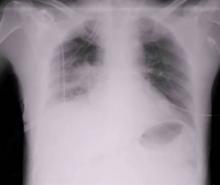

This video demonstrates a lobectomy performed through a transcervical incision without sternal lifting or retracting.